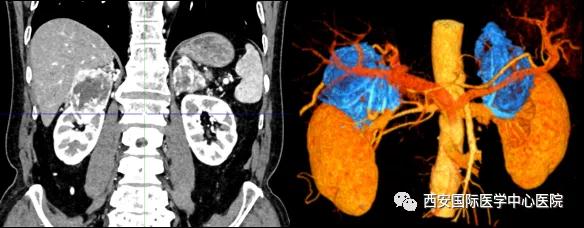

患者一家慕名前來到西安國際醫(yī)學(xué)中心醫(yī)院找到楊增悅教授。楊增悅教授仔細(xì)看完患者的之前的影像學(xué)及病理資料后,診斷為:右腎透明細(xì)胞癌(T4N1M1);并安排他住院。而后,主管醫(yī)生及時(shí)為他完善了術(shù)前檢查及評估。7月15日,在麻醉手術(shù)中心柴偉主任、王彬榮副主任、李娟護(hù)士長、李瑞剛護(hù)士長及全體麻醉手術(shù)中心團(tuán)隊(duì)的有力保障下,成功完成了這臺(tái)“大”手術(shù)。

手術(shù)由楊增悅教授主持,舒濤主治醫(yī)師、王東主治醫(yī)師主刀,黃怡醫(yī)師、王平醫(yī)師協(xié)助完成。由于第四代達(dá)芬奇機(jī)器人更加靈活和精準(zhǔn)的特性,手術(shù)全程順利,尤其是完全精準(zhǔn)的“解鎖”了右腎動(dòng)脈和右腎靜脈的數(shù)十根交互纏繞的分支血管。術(shù)后患者麻醉恢復(fù)后生命體征平穩(wěn),順利返回泌尿外科普通病區(qū)進(jìn)一步康復(fù)。